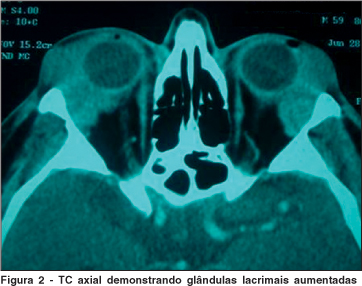

A tomografia computadorizada (TC) axial demonstrou um aumento de volume, simétrico, de ambas as glândulas lacrimais, com limites definidos e valor de atenuação misto, apresentando em sua região central atenuação reduzida e borda com atenuação mais elevada, impregnando-se levemente pelo contraste (Figura 2). O laudo radiológico sugeriu diagnóstico de dacrioadenite crônica de causa a esclarecer. A radiografia de tórax, bem como hemograma e coagulograma estavam normais.

Tomografia computadorizada, ressonância magnética e ecografia auxiliam na determinação do tamanho, número e grau da infiltração destas lesões. A maioria das lesões linfóides dos anexos oculares são massas homogêneas, unifocais, de densidade relativamente alta, geralmente se localizam dentro do tecido adiposo da órbita e tendem a se moldar às estruturas da órbita. Destruição óssea ou infiltração apenas são observadas em linfomas de alto grau(13). A tomografia realizada na avaliação inicial revelava aumento de volume homogêneo das glândulas lacrimais, de densidade elevada e sem sinais de lise óssea.